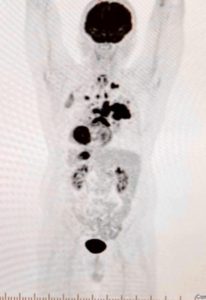

Un utilisateur a rapporté une amélioration notable de sa santé après avoir utilisé Spooky2 Central, avec une diminution significative des marqueurs cellulaires anormaux après six semaines de traitement dans le cadre de son protocole de guérison naturelle.

Mon expérience avec Spooky2 Central : Une amélioration surprenante !

J’ai choisi la thérapie métabolique et les herbes naturelles au lieu des traitements conventionnels contre le cancer. A ce jour, la maladie nodulaire a disparu et la tumeur est stable. J’ai ajouté Spook2 Central à ces protocoles il y a 6 semaines. Au départ